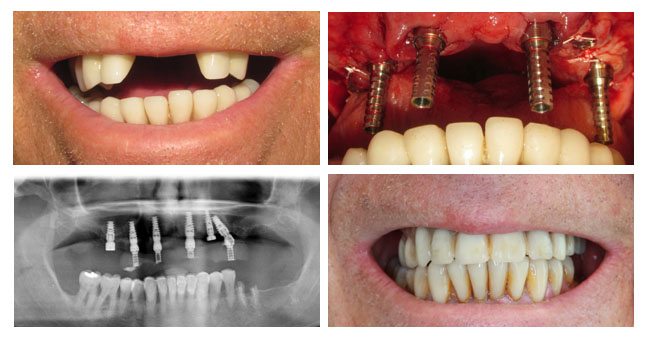

Upper Arch Extraction, Immediate Implant Placement, and Immediate Conversion Denture to Fixed Bridge in One Appointment